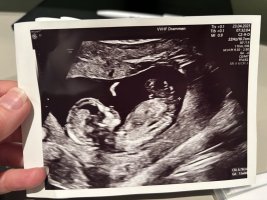

Dette må da være en gutt?Noen som vil tolke denne? 15+4. Vis vedlegget 459049

Ser ut som jenta vår, jeg tipper jente

Alle har sagt jente, kanskje jeg må begynne å tro på det?